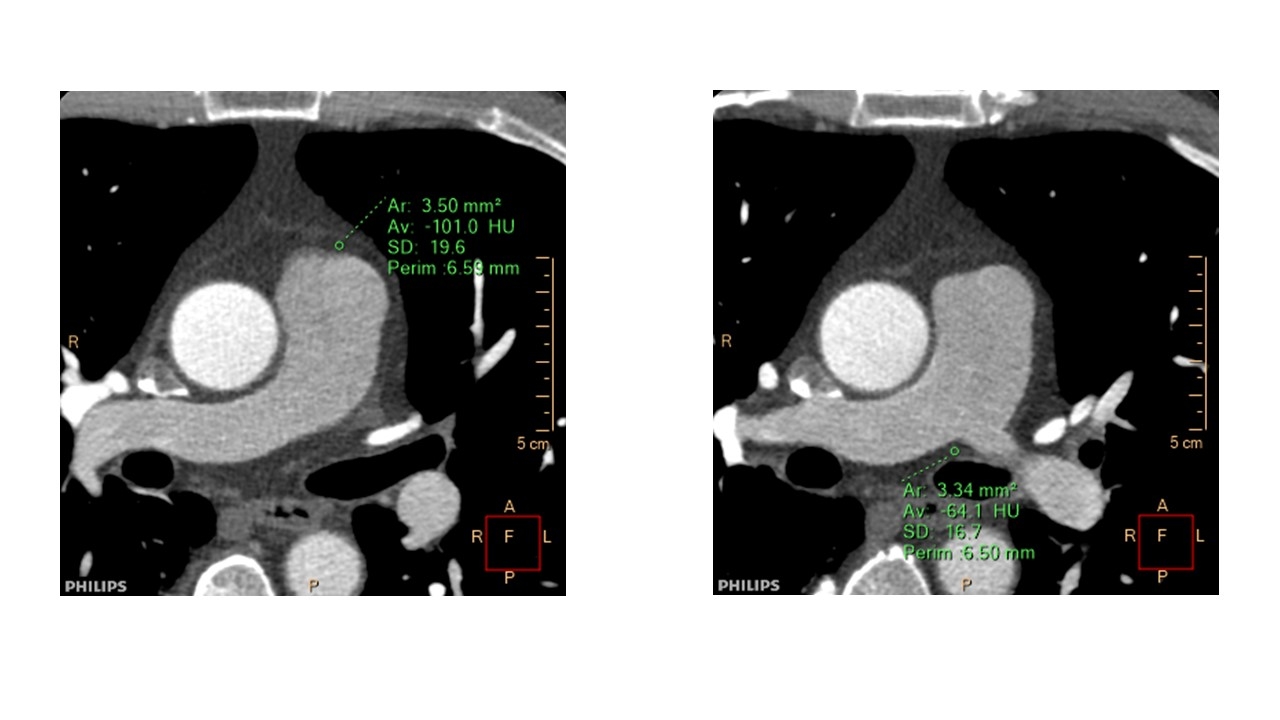

Methods: This is a retrospective analysis of 20 patients (7 male, mean age 54 year old) who underwent dual energy CT (7500, Philips) because of clinically suspected coronary artery diseases, but no significant stenosis in the coronary arteries on CT, and with normal ECG and transthoracic echocardiogram findings. From non-contrast and contrast data, presence of PA wall calcification, PA wall thickness in pulmonary trunk and proximal right PA. Furthermore, EANs and EDs (% electron density relative to water) of peri-PA adipose tissue were determined at two sites in each patient as represented in Figure 1. We compared tricuspid regurgitation pressure gradient (mmHg).

Results: On CT,no one showed PA wall calcification and mean PA wall thickness in pulmonary trunk and proximal right PA was 1.2±0.1mm. Mean EANs, and EDs of peri-PA adipose tissue at corresponding sites, were 6.15, and 6.52 (EANs), and 93.2 and 94.9 at in site 1 and 2, respectively in non-contrast phase, and 6.32, and 6.82 (EANs) in site 1 and 2, respectively in early phase. Correlation coefficients of each EAN and ED against tricuspid regurgitation pressure gradient on transthoracic echocardiogram were -0.04 and -0.13 (EANs), and 0.10 and 0.01 at in site 1 and 2, respectively in non-contrast phase, and -0.18 and -0.02 (EANs), and 0.18 and -0.24 at in site 1 and 2, respectively in early phase (Figure 2 and 3).